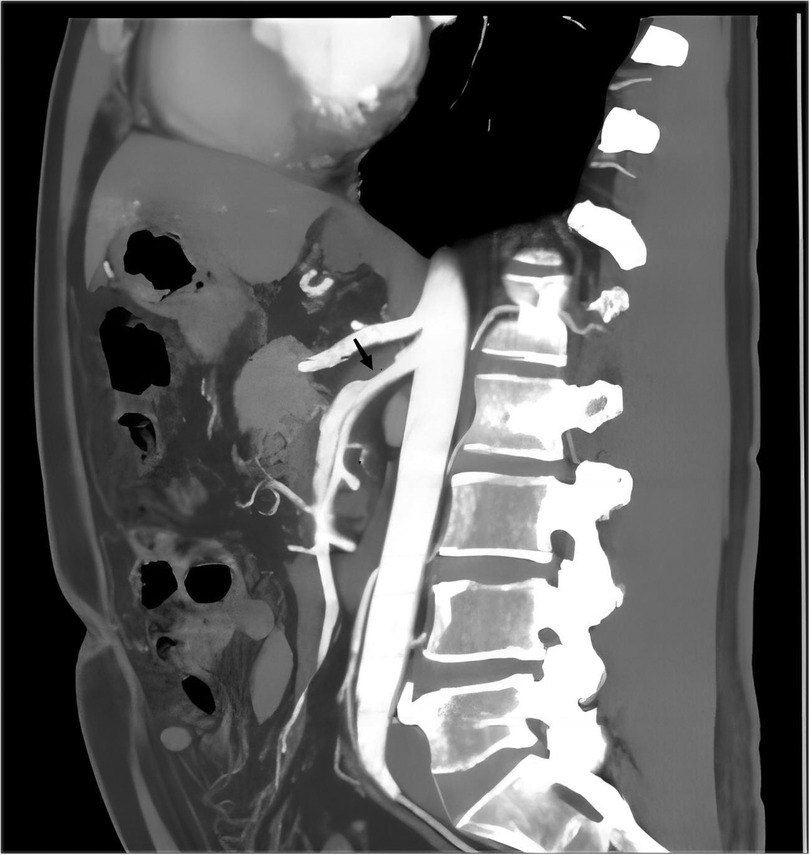

This study is a two-center case control study. The study included a total of 60 patients diagnosed with ISMAD using CTA (Figure 1). Diagnosis of ISMAD was confirmed when one of the following signs was seen in the SMA on the initial CT scan: (1) intimal flap and contrast enhancement within the false lumen; (2) crescent-shaped area along the wall of the SMA with higher attenuation than blood, showing no contrast enhancement after intravenous administration of contrast material (7, 15, 16). In our screening of patients with superior mesenteric artery dissection, we excluded those with a history of aortic dissection, major abdominal trauma, endovascular procedures for SMA, superior mesenteric artery embolism or thrombosis, connective tissue disorders, vasculitis, or intramural hematoma of the superior mesenteric artery. Finally, 60 patients constituted the study population. Clinical information of each patient was obtained including demographics, symptoms, comorbidities, treatment, and outcomes from the electric medical records. Among them, 41 patients were recruited from our center, and an additional 19 patients were recruited from another center. The control group for this study consisted of 60 individuals from our center with normal superior mesenteric artery and aorta. The age, sex and BMI of the control group were matched with ISMAD group. Their anatomical data, obtained through CTA, were included for comparative analysis.

Figure 1. The typical performance of ISMAD in the sagittal plane of a computed tomography scan, with the black arrow pointing to the location of the dissection.